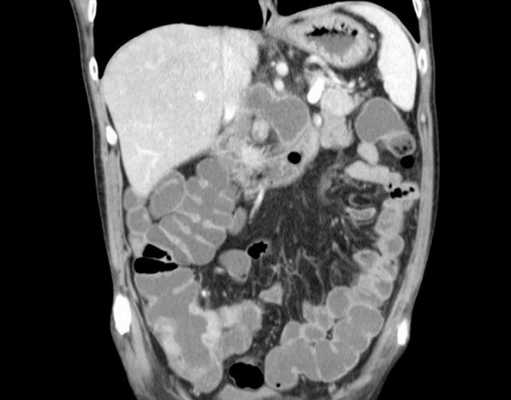

Что покажет КТ кишечник

КТ кишечника применяется для исследования толстого и тонкого кишечника, желудка, лимфатических узлов, соседних сосудов путем их сканирования с помощью рентгеновских лучей. В результате диагностики врач получает серию снимков, отображающих состояние органов ЖКТ по срезам. Метод относится к наиболее точным и высокоинформативным видам неинвазивного обследования и без внутреннего вмешательства в организм позволяет определить многие патологические процессы даже на начальном этапе, когда еще нет клинических признаков проявления недуга.

Что покажет КТ кишечника

Компьютерная томография кишечника лучше всего предназначена для определения непроходимости кишки и выявления объемных образований и патологий всех стенок кишечника. Кроме того, данное исследование помогает определить воспалительные процессы и язвенные очаги. Лечащий врач может выдать пациенту направление на КТ обследование нужного участка кишечника для проведения дифференциальной диагностики: